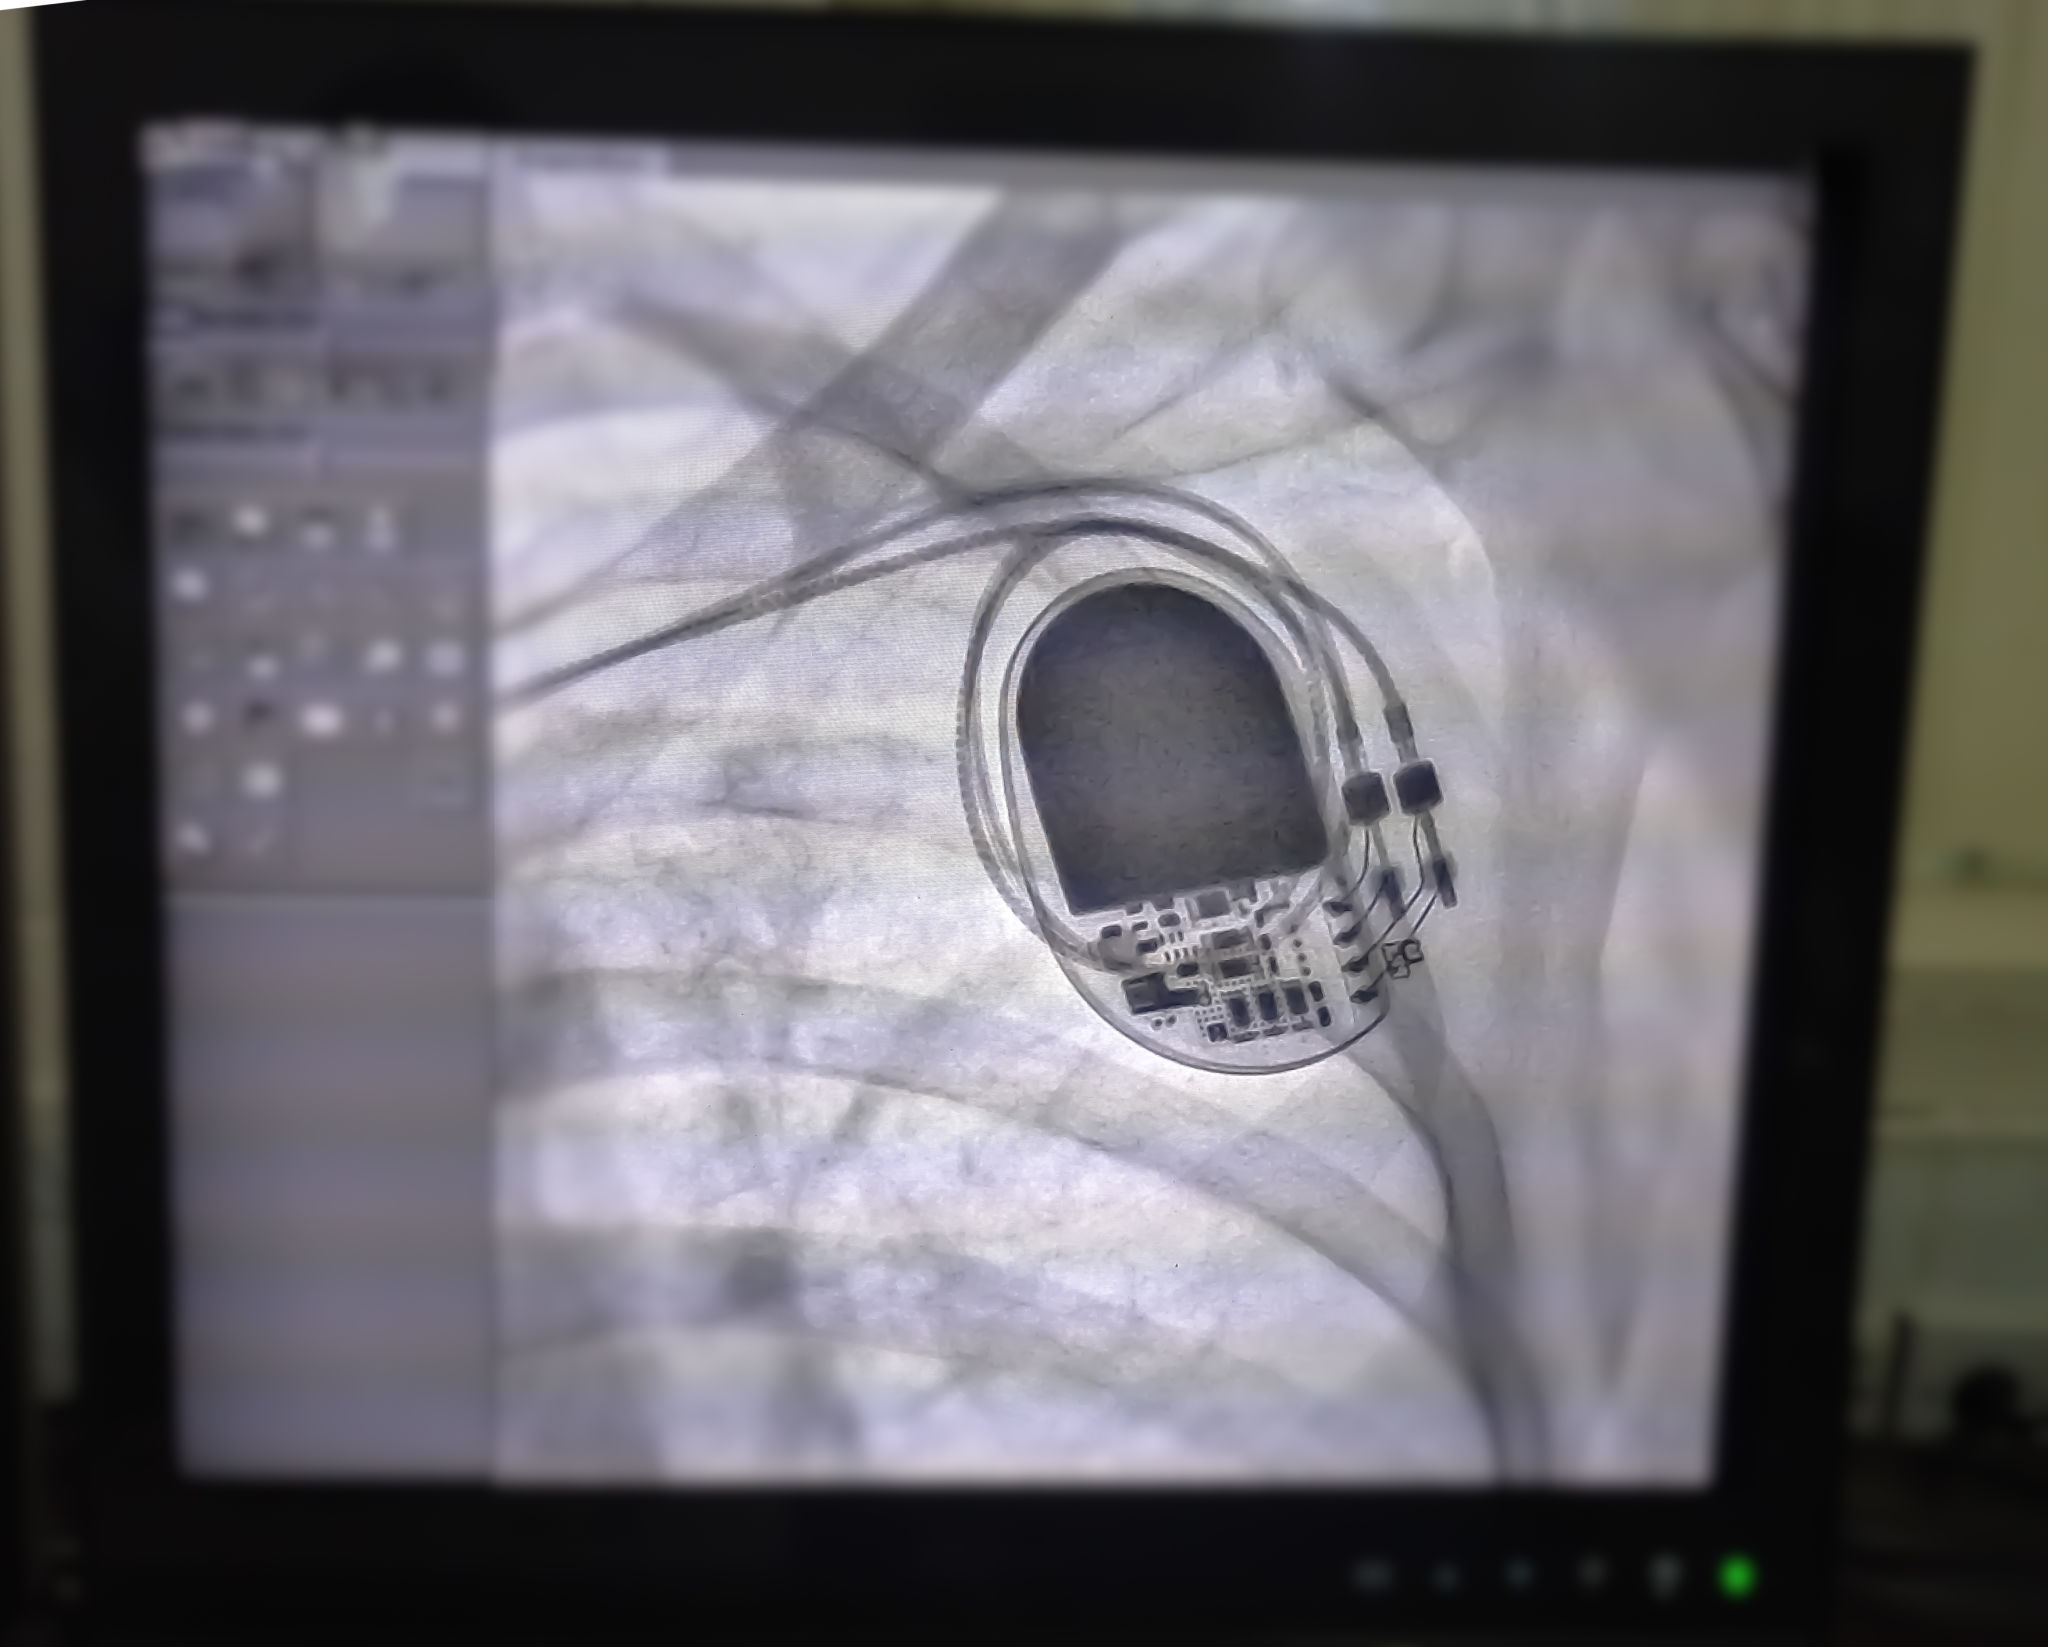

In cardiology, electrophysiological studies (EPS) are used to assess the electrical activity and pathways of the heart. This information helps in identifying abnormal heart rhythms and determining the most effective treatment options, such as medication, lifestyle changes, or surgical interventions.

- Electrocardiogram (ECG): A test that records the electrical activity of the heart over a period of time.